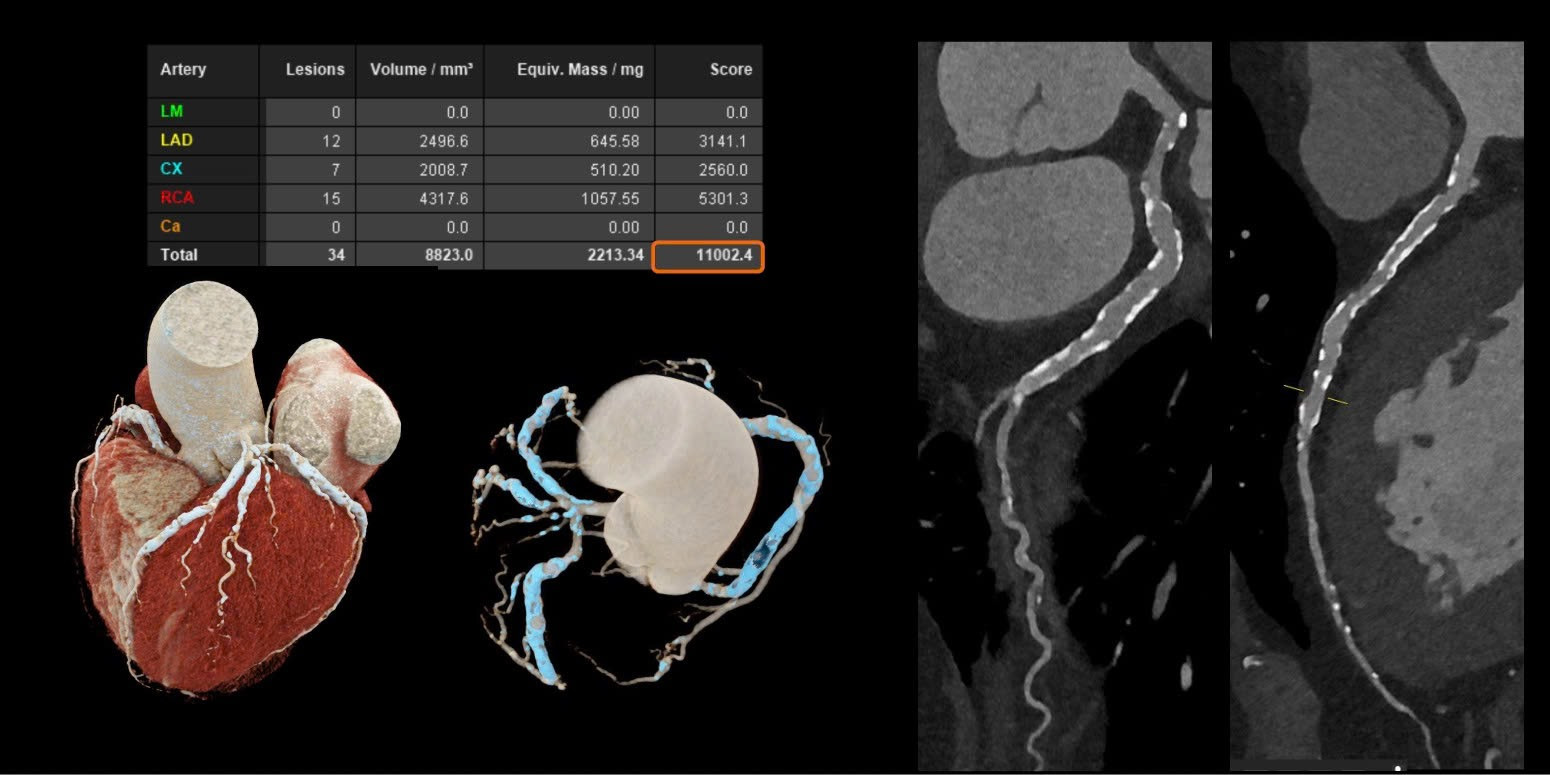

Với các bệnh tim mạch, đặc biệt ở những bệnh nhân đã đặt stent hoặc có mạch vành bị vôi hóa nặng - vốn là những trường hợp khó đánh giá bằng CT thông thường. Công nghệ này cho phép hình ảnh rõ ràng hơn đáng kể. Nhờ đó, bác sĩ có thể quan sát chính xác lòng mạch và các mảng xơ vữa, ngay cả khi bệnh nhân có nhịp tim cao hoặc loạn nhịp mà không cần sử dụng thêm thuốc hỗ trợ.